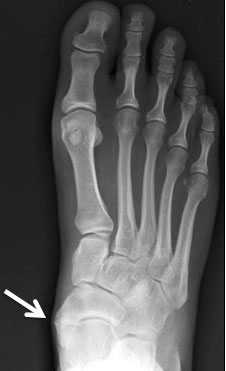

Добавочная ладьевидная кость классифицируется в соответствии с рентгенологическими ее особенностями:

- Сесамовидная косточка в толще сухожилия задней большеберцовой мышцы в области его прикрепления к ладьевидной кости

- Добавочная ладьевидная кость, сочленяющаяся синхондрозом с ладьевидной костью

- Костный выступ ладьевидной кости

Рентгенограмма стопы при 1 типе добавочной ладьевидной кости

Рентгенограммы стоп: 3 тип добавочной ладьевидной кости